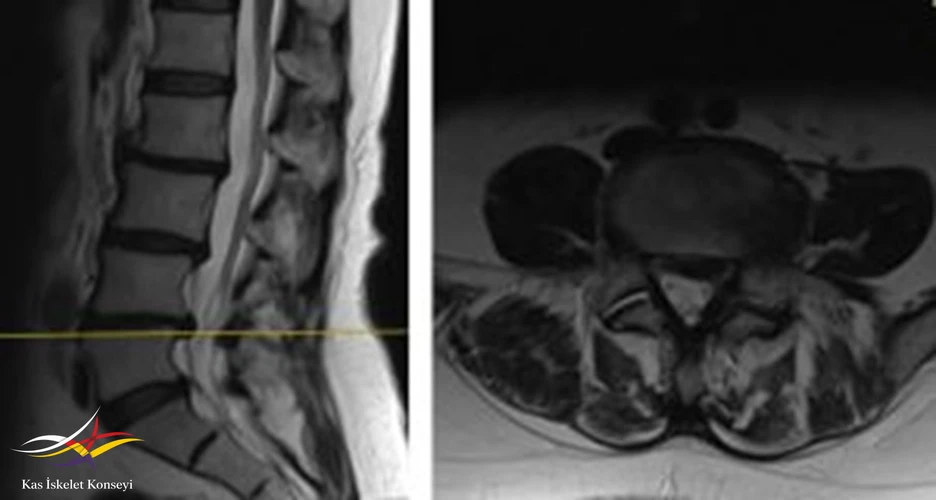

İncelemeler: Lomber MRG: L4-5 diskal bulging ve sol foraminal stenoz var. Kalça MRG istendi, iki yanlı trokanterik bursit rapor edildi.